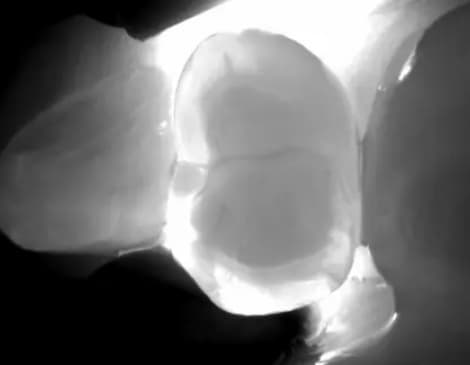

KAVO DIAGNOCAM SIN RAYOS X

Esta cámara nos permite detectar de forma fiable los primeros signos de caries mediante una combinación de imágenes intraorales, de transiluminación y de fluorescencia...